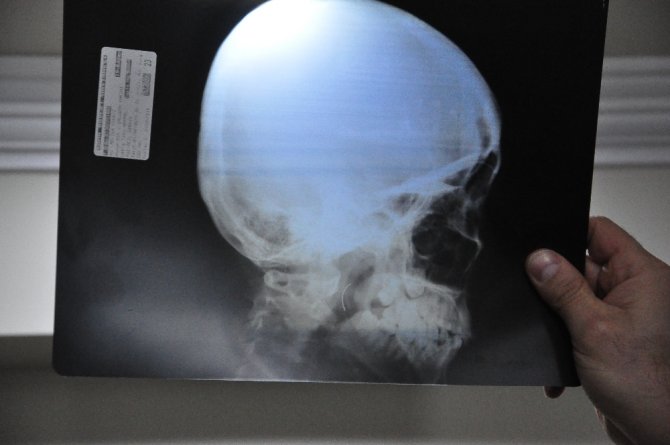

Soma Devlet Hastanesi'nde bademcik şikayetiyle 1999 yılında ameliyat olan Meltem Cansız'ın boğazında iğne unutuldu. 18 yıl boyunca boğazında iğne ile yaşayan ve şu anda 21 yaşında olan Meltem Cansız'ın tüm hayatı acı ve ağrılarla geçti. Boğazındaki iğnenin acıları günden güne yıldan yıla artan Meltem Cansız, 11 yıl sonra 14 yaşında iğnenin fark edilmesiyle Ege Üniversitesi'nde bıçak altına yattı ancak ameliyatı başarısız geçti. Lise öğreniminden sonra sağlık sorunları nedeniyle üniversiteye hazırlanamayan Meltem Cansız, acılarına rağmen yılmadı sabırla bekledi ve geçirdiği başarılı ameliyatla o iğneden 18 yıl sonra kurtuldu.

Boğazındaki iğneyle geçen 18 yılını anlatan Meltem Cansız, "3 yaşında geçirdiğim bademcik ameliyatında iğne boğazımda unutulmuş. Daha sonra iğneden dolayı 11 yıl sonra 14 yaşındayken kulak rahatsızlığım ortaya çıktı. Kafamın sağ tarafı ağrımaya başladı. Doktora gittik, hiçbir şey olmadığını söylediler. Sonrasında beni MR çekilmek üzere Akhisar'a yönlendirdi. Gecenin bir vakti MR'a girdim. Ancak bir türlü çekemediler. Benim üzerimde toka vs. metal bir şey olduğunu söylediler baktılar ancak bir şey yoktu. Üç yada dört defa MR'a girdim. Ancak bir türlü çekemediler. Sonra doktorumuz röntgene yönlendirdi. Röntgen görüntüsünde ameliyattan kalma bir çengelli iğnenin boğazımda olduğu görüldü. Bunun için beni Ege Üniversitesi'ne sevk ettiler. Burada doktorlar bu ameliyatı yapabileceklerini ancak riskinin çok olduğunu söylediler. Biz yine de kabul ettik. 1,5 saatlik operasyon geçirdim ancak iğneyi bulmadıklarını söylediler. 2 sene kadar araştırma yaptık. Birçok hastaneyle görüştük. Ancak ayağımda bir rahatsızlık meydana geldi. Ayağım için Ege Üniversitesi'ne gittik. Tekrardan beni ameliyat eden doktorumla görüştüm. "Seni ben ameliyat ettim, tekrardan buna kalkışamam" dedi. MR'a da giremezsin dediler. "Sen bununla yaşamayı öğren" en azından bunun için çabalama alınmaması daha iyi dediler. Ben daha genç bir kızım sonuçla bu iğneyle ömür boyu yaşayamazdım. Yaşanan bu olumsuzların ardından araştırmalarımız neticesinde en son İzmir'de özel bir hastaneye gittik. Oradaki doktorum Çağlar Çallı bey bana umut verdi. "Bu iğneyi alacağız" dedi. İnancımı kaybetmedim, sonucun ne olacağını bilmeden girdim ben o ameliyata. Ölüm, felç olma riskim çok fazlaydı. "Yaşayamayabilirsin" dediler, biz bile bile lades dedik. Sonucu da güzel oldu" dedi.

Baba Ahmet Cansız ise kızını 1999 yılında 3 yaşındayken bademcik sorunu nedeniyle Soma Devlet Hastanesi'ne götürdüğünü belirterek, "Bademcikleri nedeniyle çok sık hasta oluyordu. O günkü SSK'da doktorumuz ameliyat olması gerektiğini söyledi. Neticede ameliyat olduk. Ameliyat sonrasında aradan geçen süreçte kızım 17 yaşında geldiğinde yüzünde, sağ tarafında bir ağrının olduğunu, başının, kulağının ağrıdığını söyleyince kulak burun boğaz doktoruna gittik. İlaçlar verdi geçmedi, sonra bir daha gittik. Eklem arası bir iltihap olabilir diyerek MR istedi. Akhisar ilçesine MR çekilmeye gittik. Fakat bir türlü çekemediler. Daha sonra bir film çekildi ve iğne ortaya çıktı" diye konuştu.